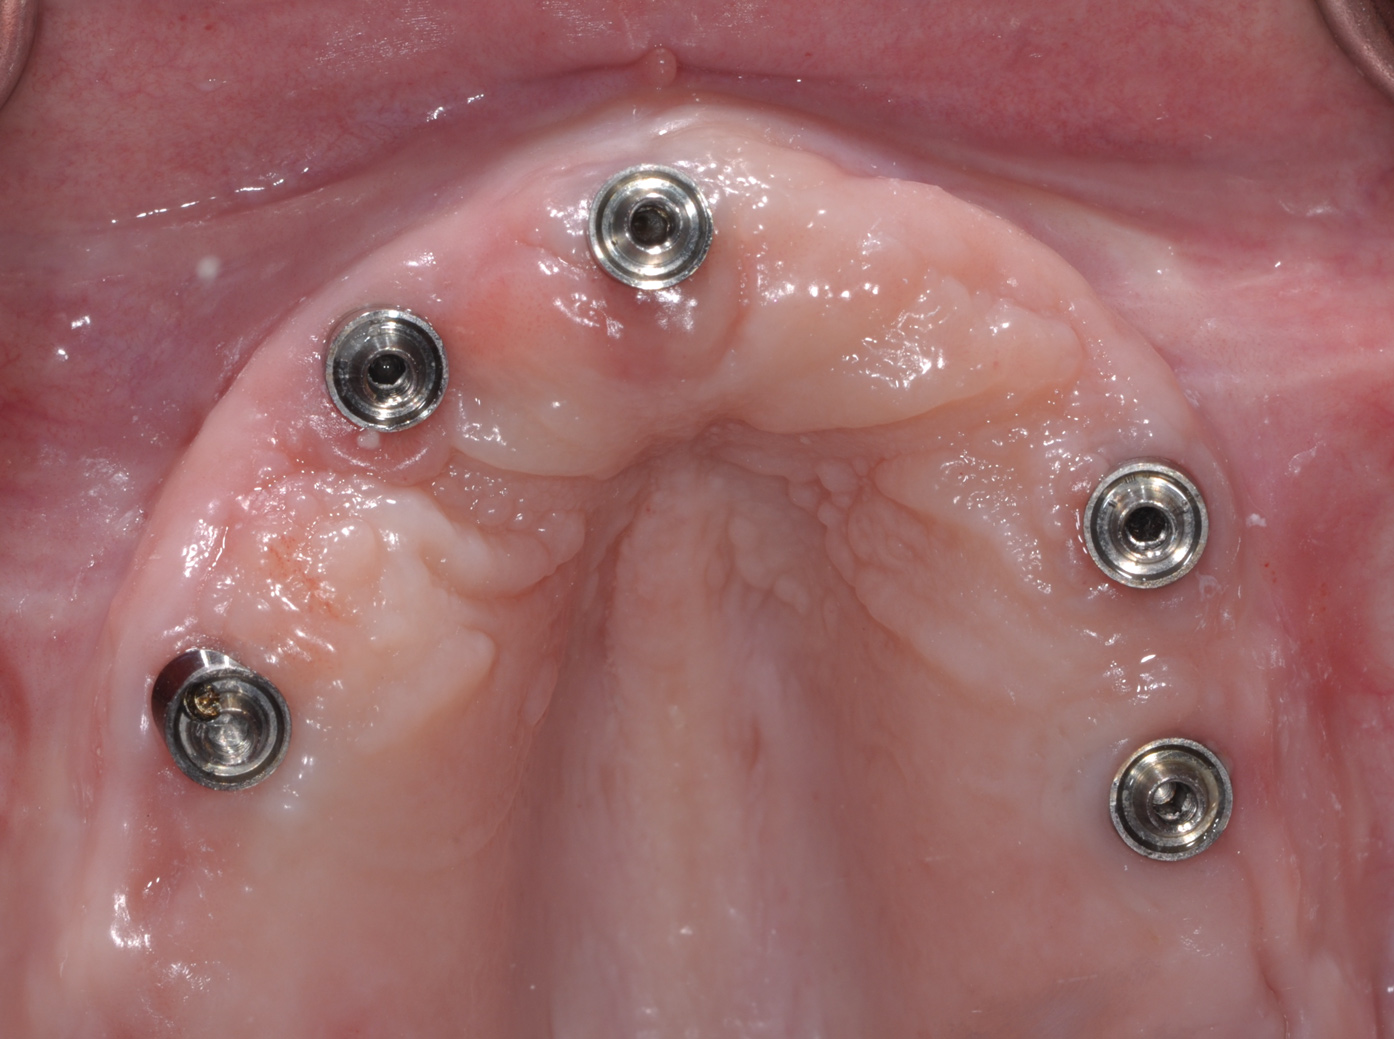

Fig 2. Upon removal of the prosthesis, plaque and debris were noted around the multi-unit abutments. Peri-implant mucositis was diagnosed.

Fig 3. Nonsurgical peri-implant treatment was performed, and the existing prosthesis was modified to enable access for patient-administered oral hygiene.

Fig 4. Four weeks after treatment, the patient presented with healthy peri-implant tissues.